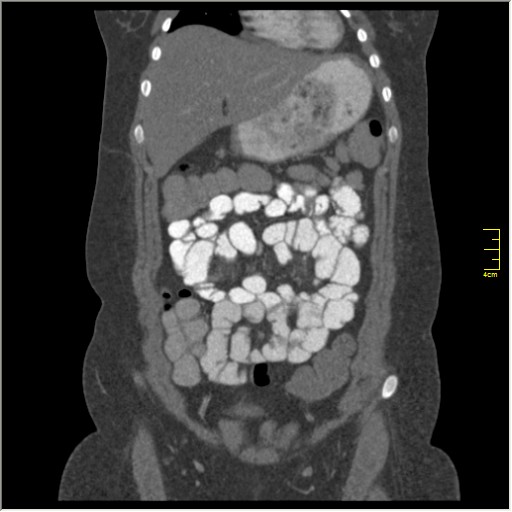

КТ энтерография

Демонстрационные изображение, оцените возможности метода! Толщина среза реконструкции 0.5-1 мм.